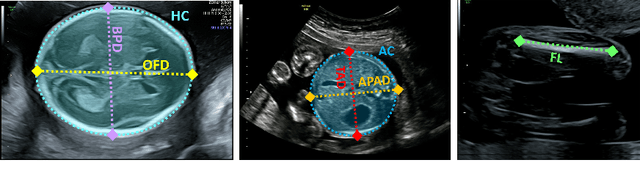

Abstract:Accurate fetal growth assessment from ultrasound (US) relies on precise biometry measured by manually identifying anatomical landmarks in standard planes. Manual landmarking is time-consuming, operator-dependent, and sensitive to variability across scanners and sites, limiting the reproducibility of automated approaches. There is a need for multi-source annotated datasets to develop artificial intelligence-assisted fetal growth assessment methods. To address this bottleneck, we present an open, multi-centre, multi-device benchmark dataset of fetal US images with expert anatomical landmark annotations for clinically used fetal biometric measurements. These measurements include head bi-parietal and occipito-frontal diameters, abdominal transverse and antero-posterior diameters, and femoral length. The dataset comprises 4,513 de-identified US images from 1,904 subjects acquired at three clinical sites using seven different US devices. We provide standardised, subject-disjoint train/test splits, evaluation code, and baseline results to enable fair and reproducible comparison of methods. Using an automatic biometry model, we quantify domain shift and demonstrate that training and evaluation confined to a single centre substantially overestimate performance relative to multi-centre testing. To the best of our knowledge, this is the first publicly available multi-centre, multi-device, landmark-annotated dataset that covers all primary fetal biometry measures, providing a robust benchmark for domain adaptation and multi-centre generalisation in fetal biometry and enabling more reliable AI-assisted fetal growth assessment across centres. All data, annotations, training code, and evaluation pipelines are made publicly available.

Abstract:Fetal growth assessment from ultrasound is based on a few biometric measurements that are performed manually and assessed relative to the expected gestational age. Reliable biometry estimation depends on the precise detection of landmarks in standard ultrasound planes. Manual annotation can be time-consuming and operator dependent task, and may results in high measurements variability. Existing methods for automatic fetal biometry rely on initial automatic fetal structure segmentation followed by geometric landmark detection. However, segmentation annotations are time-consuming and may be inaccurate, and landmark detection requires developing measurement-specific geometric methods. This paper describes BiometryNet, an end-to-end landmark regression framework for fetal biometry estimation that overcomes these limitations. It includes a novel Dynamic Orientation Determination (DOD) method for enforcing measurement-specific orientation consistency during network training. DOD reduces variabilities in network training, increases landmark localization accuracy, thus yields accurate and robust biometric measurements. To validate our method, we assembled a dataset of 3,398 ultrasound images from 1,829 subjects acquired in three clinical sites with seven different ultrasound devices. Comparison and cross-validation of three different biometric measurements on two independent datasets shows that BiometryNet is robust and yields accurate measurements whose errors are lower than the clinically permissible errors, outperforming other existing automated biometry estimation methods. Code is available at https://github.com/netanellavisdris/fetalbiometry.

Abstract:During pregnancy, ultrasound examination in the second trimester can assess fetal size according to standardized charts. To achieve a reproducible and accurate measurement, a sonographer needs to identify three standard 2D planes of the fetal anatomy (head, abdomen, femur) and manually mark the key anatomical landmarks on the image for accurate biometry and fetal weight estimation. This can be a time-consuming operator-dependent task, especially for a trainee sonographer. Computer-assisted techniques can help in automating the fetal biometry computation process. In this paper, we present a unified automated framework for estimating all measurements needed for the fetal weight assessment. The proposed framework semantically segments the key fetal anatomies using state-of-the-art segmentation models, followed by region fitting and scale recovery for the biometry estimation. We present an ablation study of segmentation algorithms to show their robustness through 4-fold cross-validation on a dataset of 349 ultrasound standard plane images from 42 pregnancies. Moreover, we show that the network with the best segmentation performance tends to be more accurate for biometry estimation. Furthermore, we demonstrate that the error between clinically measured and predicted fetal biometry is lower than the permissible error during routine clinical measurements.